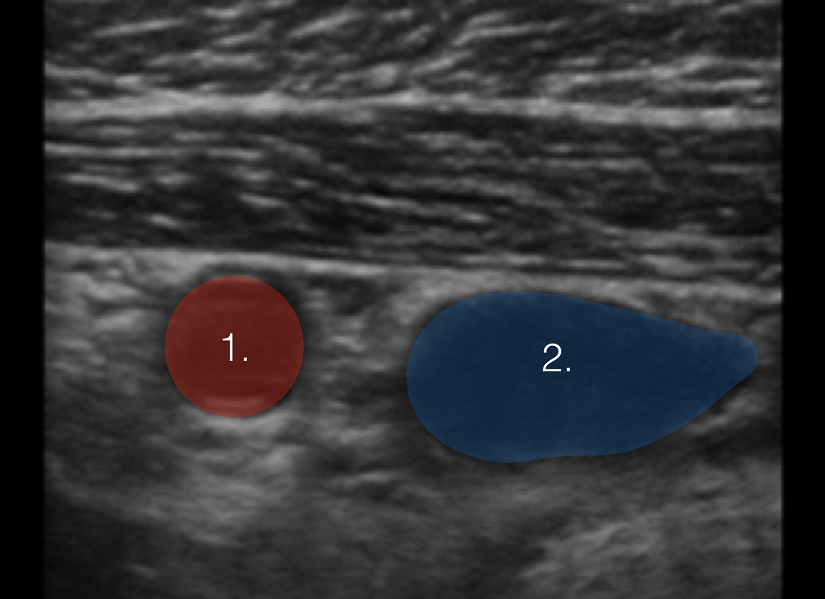

血管识别图像

动脉

静脉